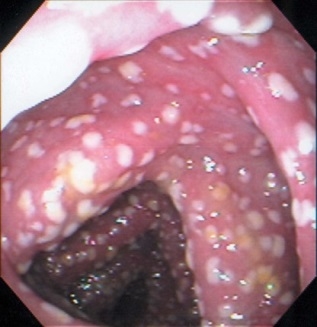

艰难梭菌感染患者可以从无症状的细菌定植到腹泻(大于等于3次/天)并伴有发热、腹痛、腹胀、恶心和呕吐等全身性感染症状,重症患者可进一步发展成伪膜性肠炎、中毒性结肠、肠道穿孔、脓毒性休克,甚至死亡。

从症状上看,和炎症性肠病常见症状高度重合。所以艰难梭菌容易成为漏网之鱼,应提高对艰难梭菌引起腹泻等相关症状的敏感性。